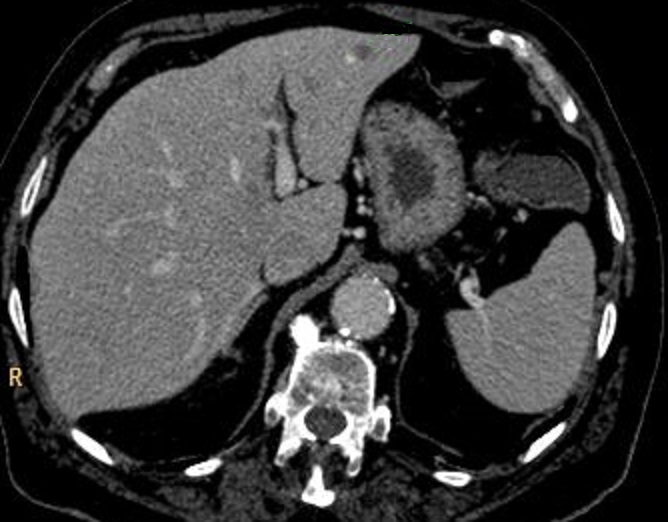

Image

radiologique TDM du lesion malignite a extension

metastase hepatique d'une

tumeur intracanalaire

papillaire et mucineuse du pancréas ( TIPMP ) .

la tumeurs de latete du pancreas est volumineuse , a

bord irregulie , canal principale dilate et il

y avait de plusieure des nodules metastatiques

hypodense du foie droit . Image TDM en coupe axiale |